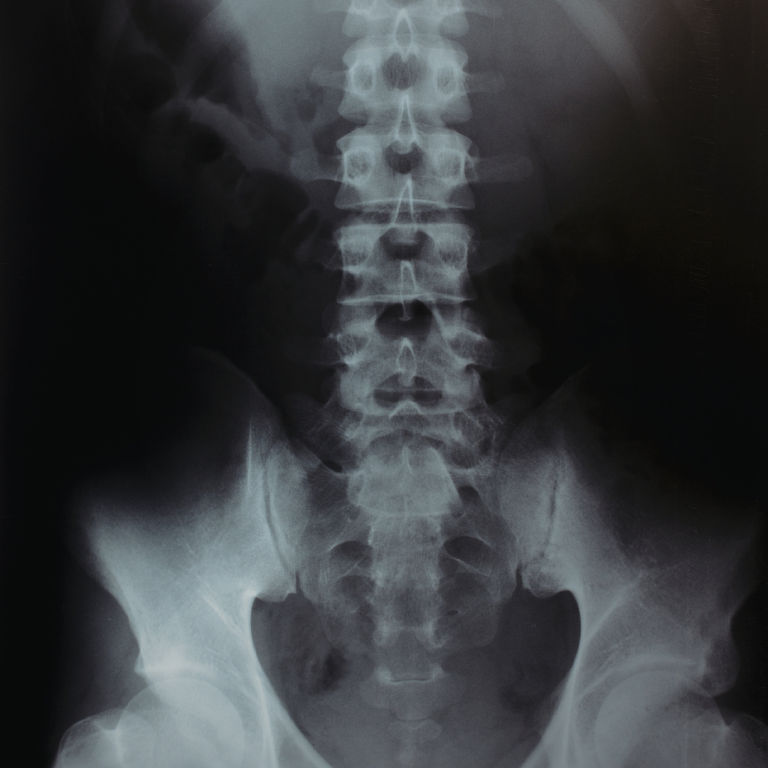

Radiografie:

• Ce poți evalua: aliniament, scolioză, cifoze/lordoze, spondilolistezis

• Când este utilă radiografia dinamică (flexie–extensie)

Lecția 9 – Instabilitatea segmentară și spondilolistezisul

Tipuri de spondilolistezis

• Degenerativ

• Congenital

• Post-traumatic

Instabilitatea dinamică

• Ce arată radiografia în flexie-extensie

• Diferența între RMN (static) și radiografie dinamică

• Semne imagistice de instabilitate